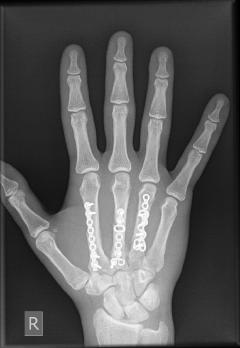

Κατάγματα δακτύλων της άκρας χειρός

Τα εν λόγω κατάγματα είναι συχνά σε νέους ενήλικες, ειδικά χειρώνακτες, καθώς και σε αθλουμένους και μπορεί να είναι μέρος βαρύτερων και πλέον σύνθετων τραυματισμών, που περιλαμβάνουν τένοντες, αγγεία, νεύρα. Οι περιπτώσεις που αντιμετωπίζονται χωρίς χειρουργική επέμβαση είναι λίγες. Ως υλικά οστεοσύνθεσης χρησιμοποιούνται είτε κατάλληλου σχεδιασμού μικρές πλάκες και βίδες είτε λεπτές βελόνες. ΟΙ βελόνες αφαιρούνται πολύ εύκολα μετά από λίγες εβδομάδες, ενώ τα άλλα υλικά παραμένουν και αφαιρούνται χειρουργικώς μόνο εάν χρειαστεί.

Η χειρουργική επέμβαση είναι λεπτή, γίνεται με μεγεθυντικά γυαλιά (loupes) και λεπτά εργαλεία και δεν απαιτεί παραμονή στο νοσοκομείο. Η μετεγχειρητική κινητοποίηση εξαρτάται από τον τύπο του κατάγματος, το είδος της οστεοσύνθεσης αλλά και τυχόν συμπαρομαρτούσες καταστάσεις. Δεν είναι σπάνιο να χρειάζεται περίοδος φυσιοθεραπείας στη συνέχεια.